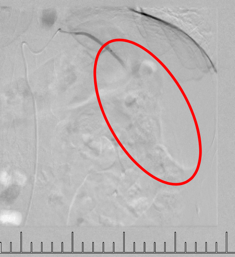

灌注藥物及栓塞后“烏云”消失

肋間動脈阻斷營養(yǎng)來源